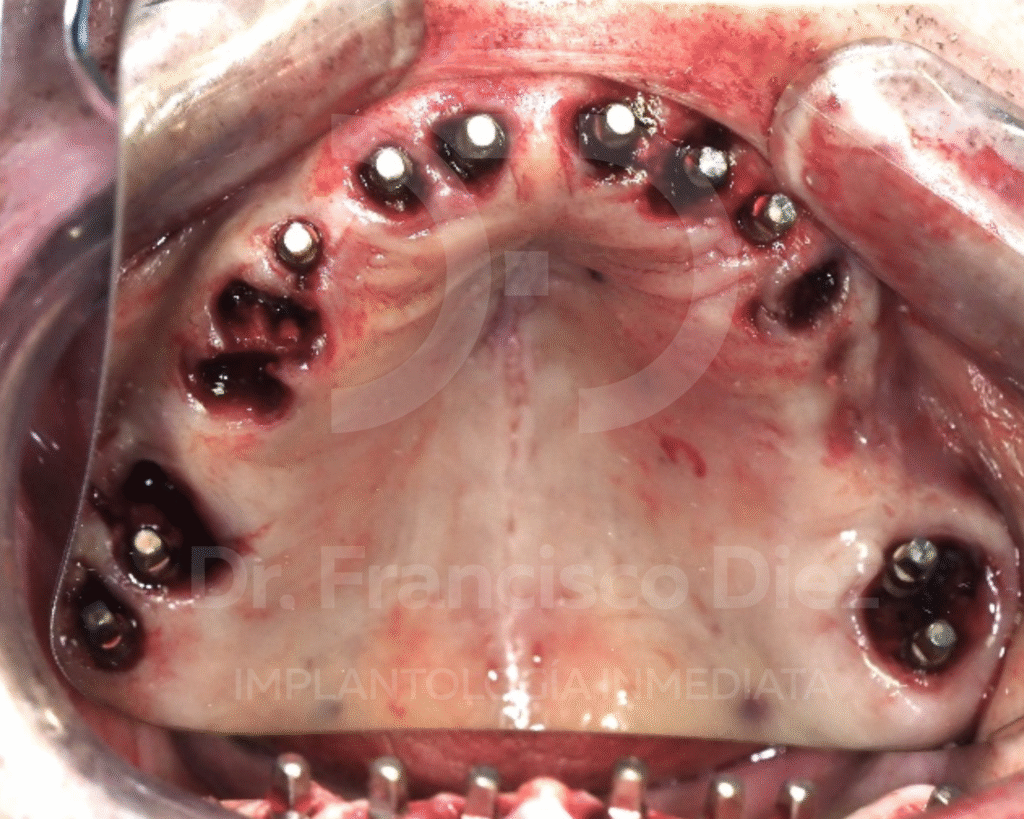

En una única intervención se procedió a la extracción de todos los dientes del maxilar superior y a la colocación inmediata de 10 implantes córticobasales BCS, anclados en hueso cortical. Esta técnica permite tratar casos con atrofia ósea severa sin necesidad de injertos, reduciendo de forma significativa la invasividad del tratamiento.